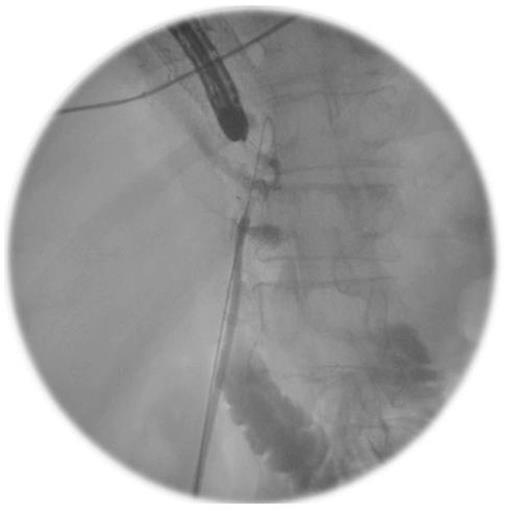

A novel approach to the management of a fistula after pyloroplasty was employed. A combined endoscopic and fluoroscopic procedure was performed where a radiologically placed snare was inserted through the abdominal drain and manipulated into the gastric tube through the defect in the pyloroplasty. A gastroscope was used to introduce a T-tube into the gastric tube and into the snare. The abdominal drain and snare were withdrawn and the T-tube placed appropriately, plugging the hole in the pyloroplasty, under direct vision. A further guide wire was left in place along the tract of the tube drain and was used to deploy a pigtail drain alongside the pyloroplasty (Figures 5 and 6).

An Intra-operative image demonstrating the combined endoscopic and fluoroscopic procedure